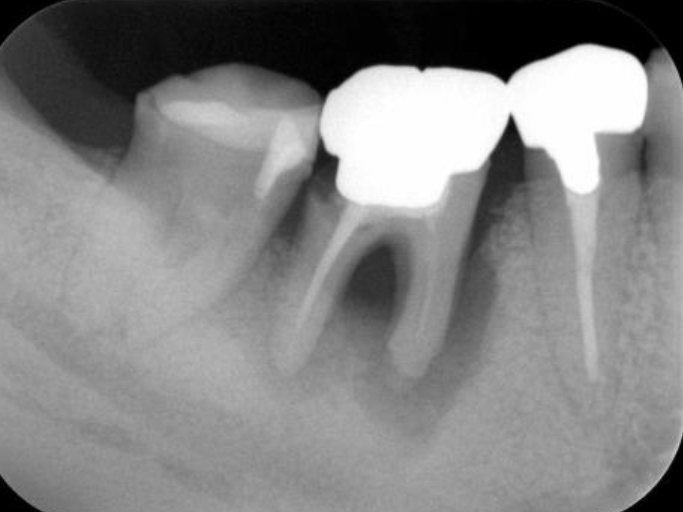

初診時(レントゲン)

歯周基本治療・根管治療後(レントゲン)

歯周外科処置後

(レントゲン)

初診時年齢:

治療:歯周病治療・う蝕治療

治療法:歯周基本治療、歯周外科治療、感染根管治療

治療期間:1年3ヶ月

費用:保険診療

リスク・副作用:歯周外科処置後に出血、腫れ、あざが出ることがありますが時間とともに治ります。術後3週間程度噛んだときの痛みや歯が浮いた感じがすることがあります。

感染根管処置中に腫れ、痛みが出ることがありますが時間とともに治ります。